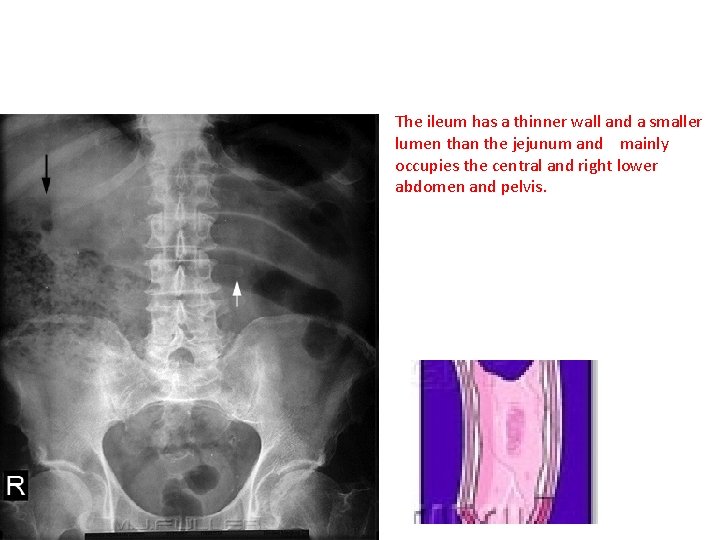

The ileum has a thinner wall and a smaller lumen than the jejunum and mainly occupies the central and right lower abdomen and pelvis.